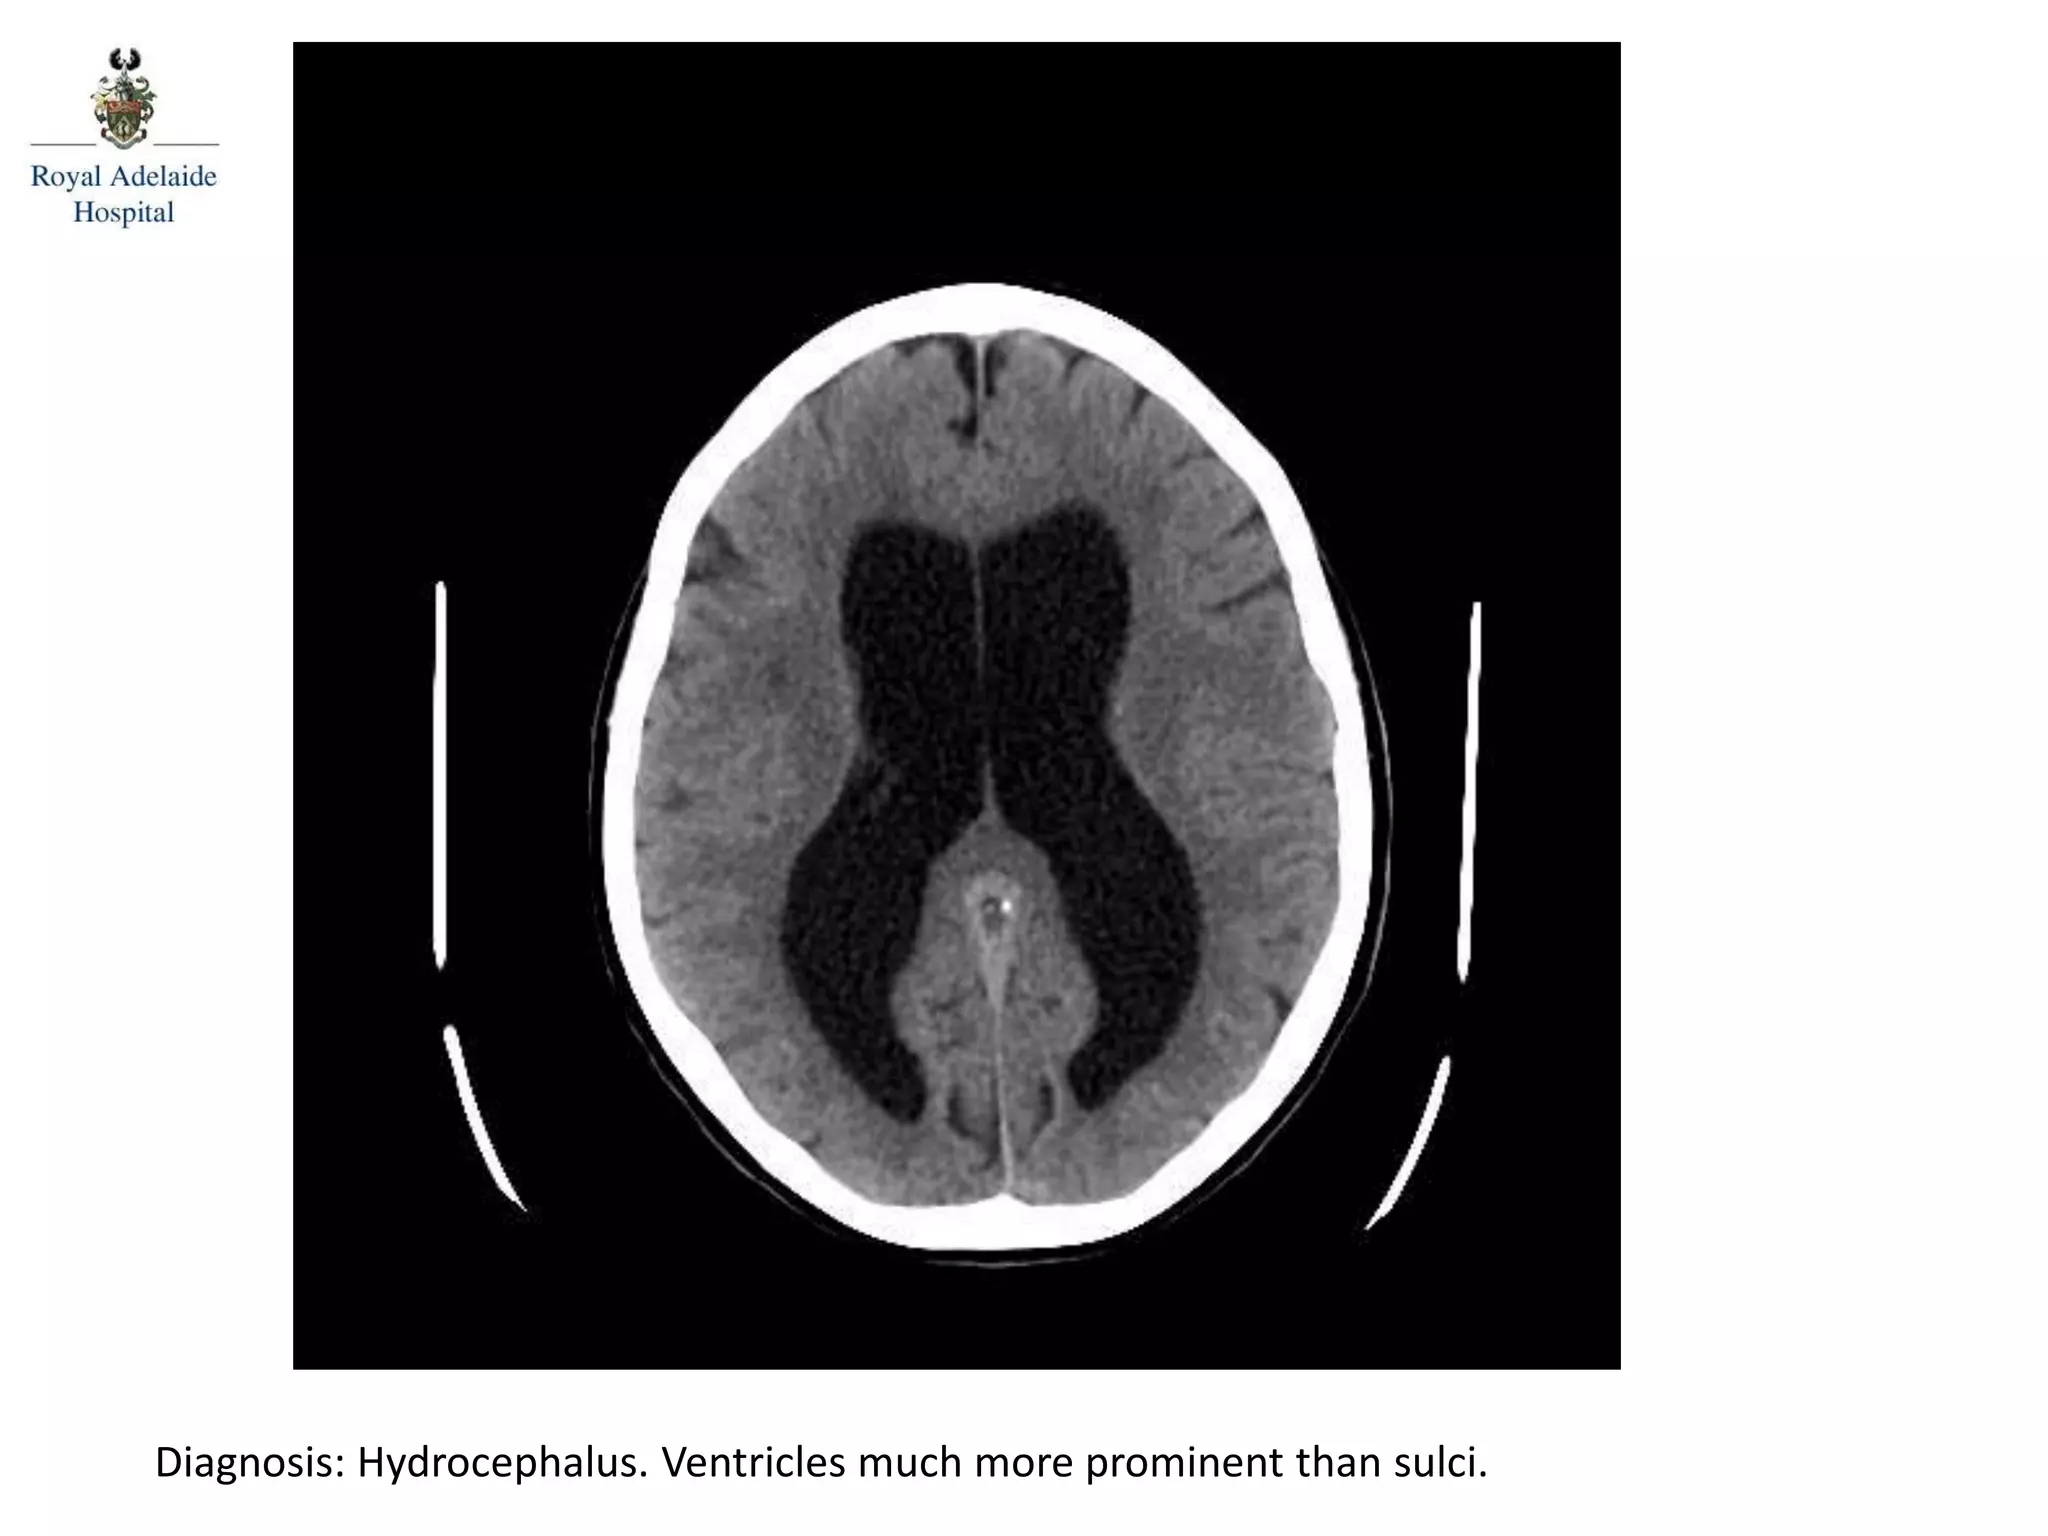

The document outlines multiple diagnoses from head CT cases, including small left basal ganglia bleed likely due to hypertension, various types of subdural and subarachnoid hemorrhages, and evidence of hydrocephalus. It details traumatic origins of some hemorrhages and notes obstructing masses and atrophic changes. Overall, there are significant findings indicating complications related to cerebral hemorrhages and ventricular enlargement.